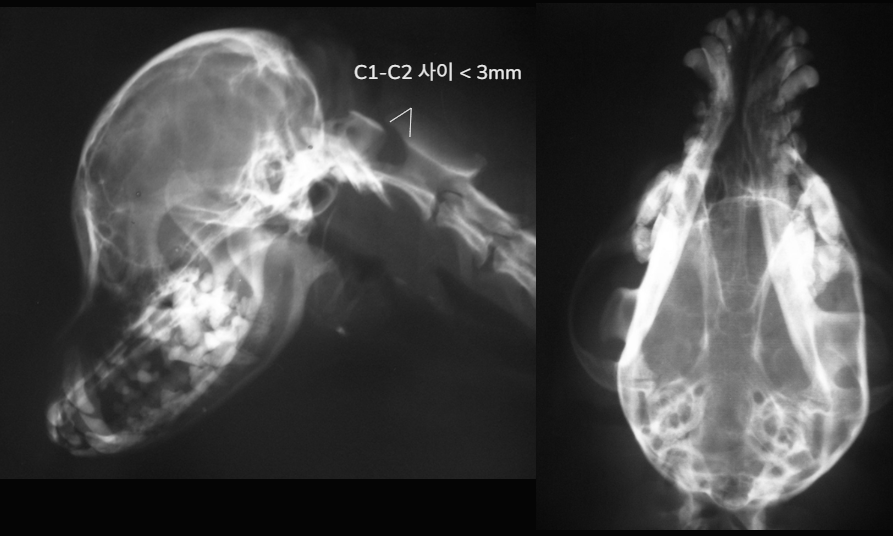

| MRI (transverse) |

![]() |

| - ๊ฐ์ชฝ๋์ค์ด ์ ์๋ณด๋ค ํ์ฅ๋์ด ์์. - Tumor ์กด์ฌ : T2 image์์ ์ข ์ ์ถ์ โ FLAIR๋ก ํ์คํ ํ์ธ - ๋์ diencepalon ์์ญ์ ํฐ tumor ์กด์ฌ (๊ฐ๋์์๋ hypothalamus๋ pituitary gland์ ์ข ์ ์์ ๊ฐ๋ฅ์ฑ ๋์ : ํธ๋ฅด๋ชฌ ์งํ(Cushingโs dz) ๊ฐ๋ฅ์ฑ ๋์ โ ๋ด๋ถ๋น ์ฆ์ ๋ณด์ผ ๊ฒ) - Hydrocephalus๋ ์ฌํ์ง ์์ ์์ค์ผ๋ก ์์ - Dural tail sign์ ๋ณด์ด์ง ์์ : Meningioma < hypothalamus tumor |

Thalamus, hypothalamus์ mass (1.5 X 1.6cm) Hydrocephalus (23%, moderate)